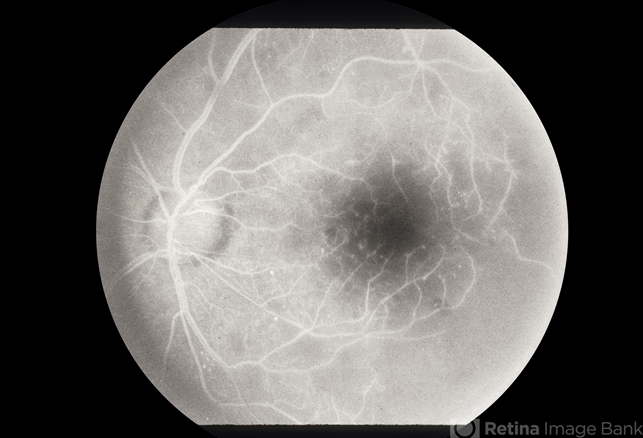

- Retinal Vascular Occlusive Disease

- retinal vascular occlusion

- 35yr old black male with retinal vascular occlusive disease.